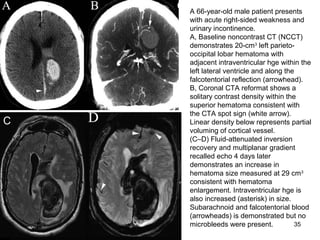

A 66-year-old male patient presents

A, Baseline noncontrast CT (NCCT)

demonstrates 20-cm3

left parieto-

occipital lobar hematoma with

adjacent intraventricular hge within the

left lateral ventricle and along the

falcotentorial reflection (arrowhead).

B, Coronal CTA reformat shows a

solitary contrast density within the

superior hematoma consistent with

the CTA spot sign (white arrow).

Linear density below represents partial

voluming of cortical vessel.

(C–D) Fluid-attenuated inversion

recovery and multiplanar gradient

recalled echo 4 days later

demonstrates an increase in

hematoma size measured at 29 cm3

consistent with hematoma

enlargement. Intraventricular hge is

also increased (asterisk) in size.

Subarachnoid and falcotentorial blood

(arrowheads) is demonstrated but no

microbleeds were present.